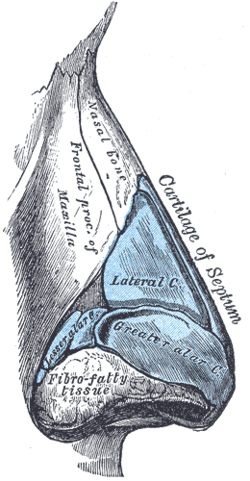

Cartilages of the nose. Side view. (Nasal bone visible at upper left.) | |

The outer surface is concavoconvex from above downward, convex from side to side; it is covered by the procerus and nasalis muscles, and perforated about its center by a foramen, for the transmission of a small vein.

The inner surface is concave from side to side, and is traversed from above downward, by a groove for the passage of a branch of the nasociliary nerve.